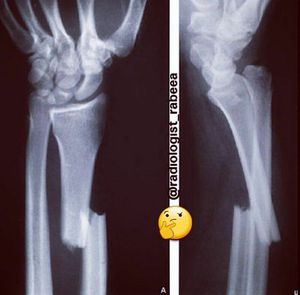

What is diagnosis?

galeazzi fracture-dislocation Smith fracture Hutchinson fracture Reverse barton fracture Barton fracture Colles fracture

Galeazzi fracture